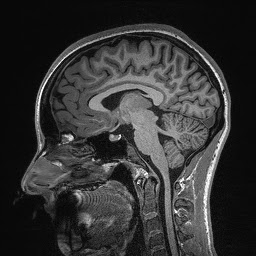

The images are taken in slices beginning from the outside and working its way in—that’s why my brain structures look smaller or bigger in some areas, and why my nose doesn’t show up until the end. And now, without further ado…my brain!

Eventually, when the lab technicians overlaid these images, they were able to create a 3D image of my entire brain, which might have looked something like this:

Pretty cool, huh?